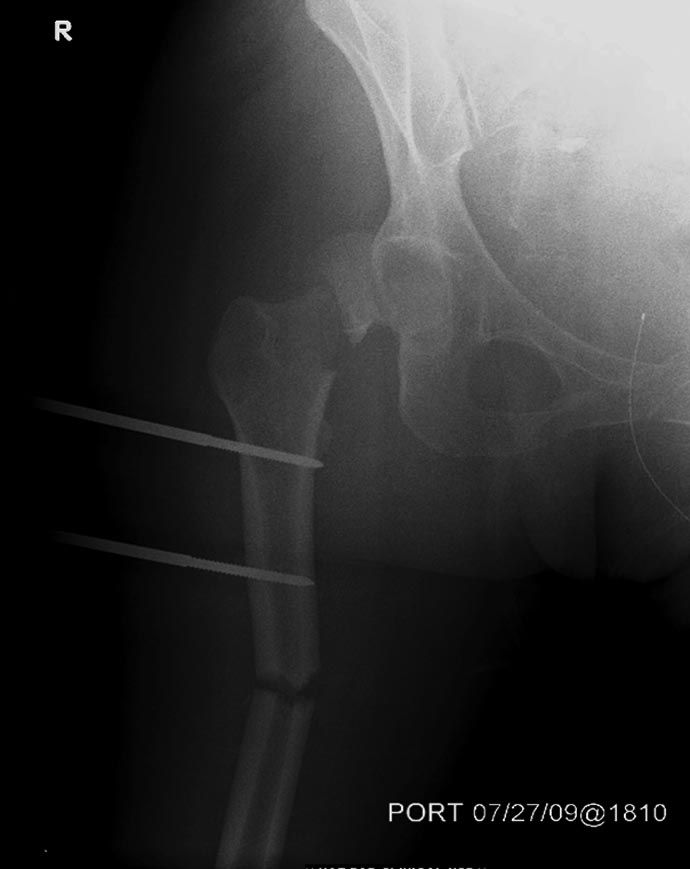

1.Вправление вывиха бедра, репозиция, остеосинтез перелома шейки бедра

3.После компенсации состояния внутренний остеосинтез диафиза и

дистального метафиза правого бедра.

В нашем случае с момента травмы прошло около 2 суток, и переломо-вывих

бедра остается не вправленный. По нашим данным, риск осложнений при

Во время совместной операции с хирургами по I&D  вакумированием раны

живота и ран конечности, смогли быстро наложить наружный фиксатор на бедро.